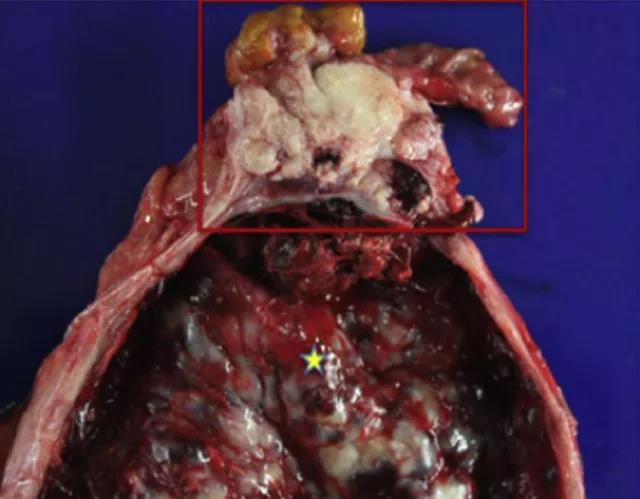

大体检查标本提示为壶腹部肿瘤,侵犯大、小乳头(图 4)。

图 4  大体标本提示扩张的胰管(星号),壶腹部肿瘤,以及切除的十二指肠(方框内)

随后予施行胰十二指肠切除术,术中证实为肿瘤堵塞胰管,导致胰管直径扩张至 17 cm,伴有腺体肥大(图 3)。